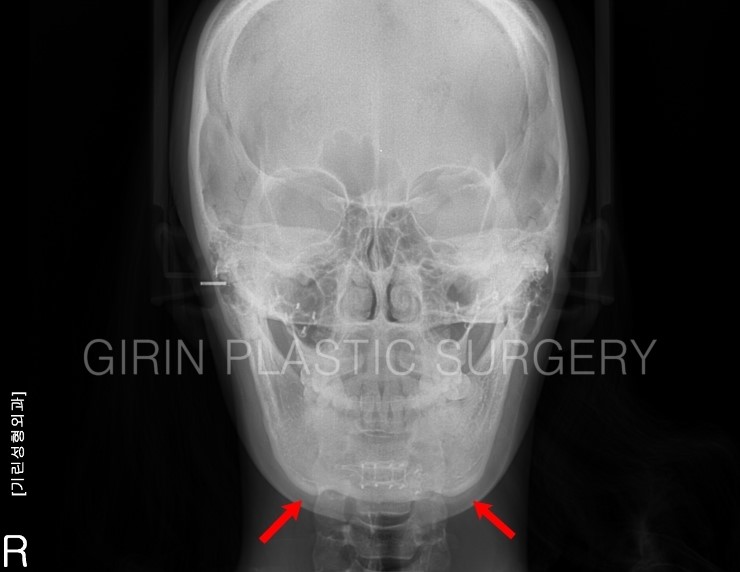

육안으로 봤을 때 앞턱이 갸름하지 않고 U라인으로 보입니다. 엑스레이를 보면 티절골 후 발생한 이차각이 확인되는데 옆모습을 보면 좀더 확실히 증상이 나타납니다.

화살표부위가 이차각이며, 귀밑각이 과절제되었습니다. 재수술로 이차각을 포함한 앞턱까지 전체적인 라인수정 필요성이 있습니다.